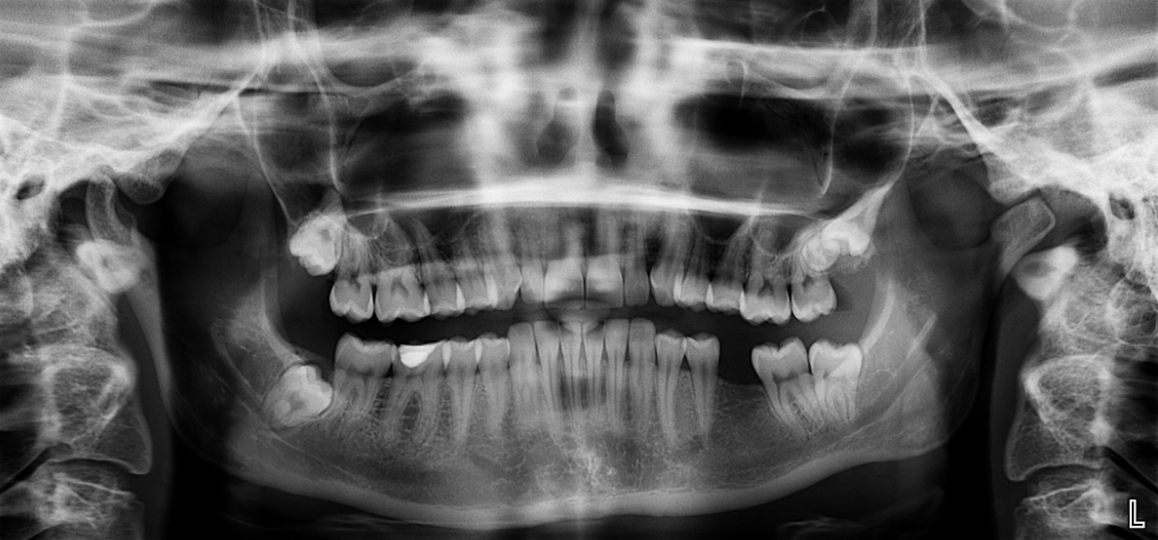

Image by peter-facebook on Pixabay